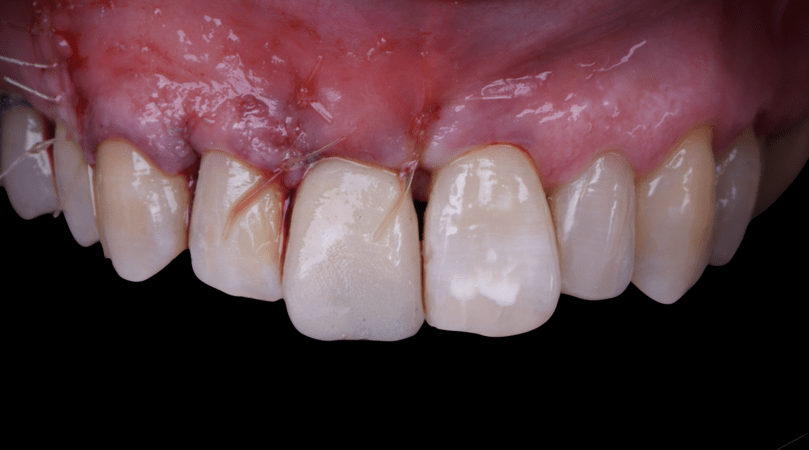

After an appropriate healing period, the definitive prosthesis was planned and delivered. A screw-retained zirconia crown was fabricated to ensure long-term durability, optimal esthetics, and retrievability. Zirconia was selected for its mechanical strength and excellent esthetic properties, blending seamlessly with the adjacent natural dentition in both form and color.

The final crown was designed to maintain the gingival architecture that had been shaped by the provisional. Special attention was paid to the emergence profile, contact points, and translucency to achieve harmony with the patient’s smile. The definitive restoration provided functional stability and esthetic integration, fulfilling the patient’s expectations for a fixed and natural solution.